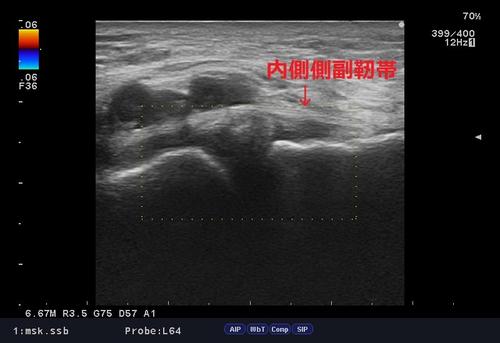

いつものように問診、触診、ストレステスト後、エコー検査。

内側側副靭帯損傷1.jpg

エコー検査では内側側副靭帯周囲、関節内の腫脹が診られ、結果「膝内側側副靭帯損傷」の疑い。